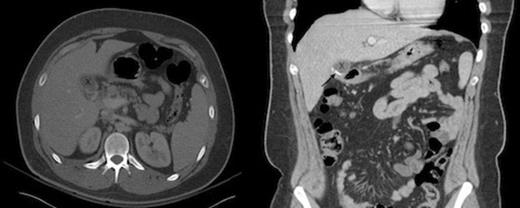

CT of the abdomen demonstrates the residual portion of the gallbladder, marked by an “X” in both the axial and coronal views. The staple line, indicated by a black arrow, is seen best on the coronal imaging